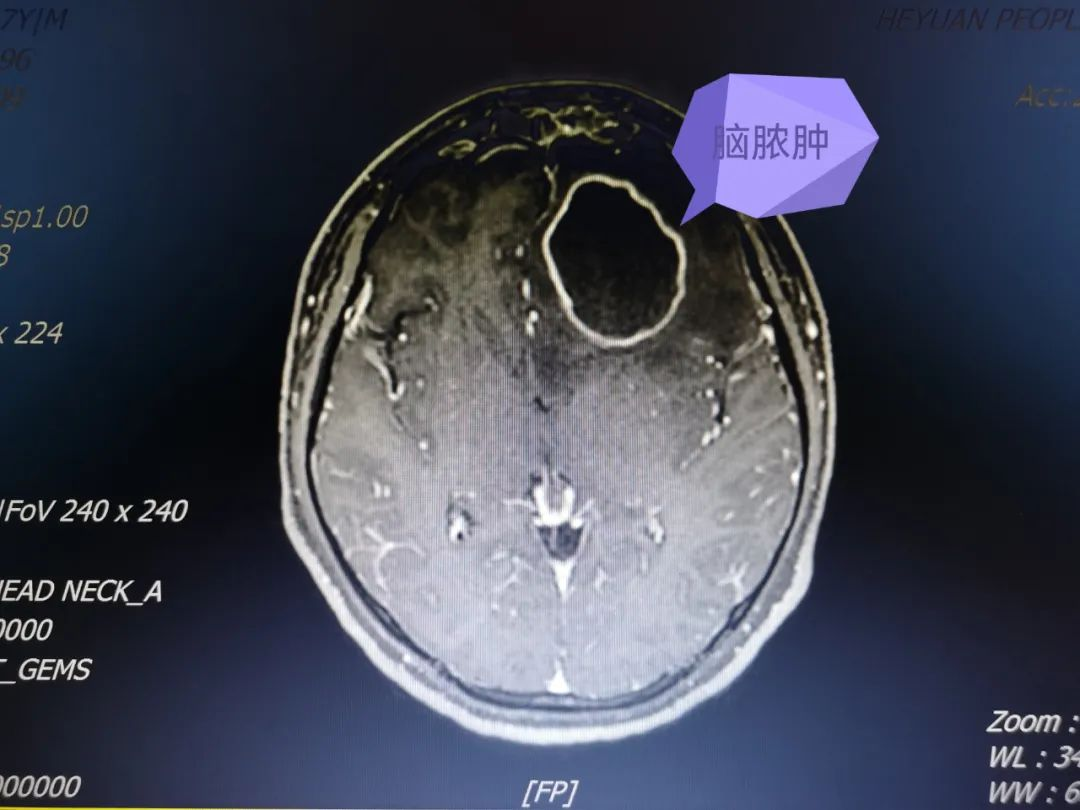

神经外科一区科主任杨建雄查房后指出:患者有明确外伤,颅底骨折并脑脊液漏病史,当地医院MRI考虑左额叶脑内血肿,要警惕脑脓肿可能,予脱水降颅压,完善颅脑MRI增强扫描。在等候检查过程中,患者病情加重,我院放射科紧急安排患者连夜检查,结果提示:1、左侧额叶脑脓肿(左侧额窦来源)并破入脑室及蛛网膜下腔,继发性化脓性脑膜炎;2、双侧额窦、筛窦、左侧上颌窦及蝶窦炎瘂,左侧额窦脓肿。MRI阅片提示脑内脓肿有如鸡蛋大小,杨建雄主任立刻组织神经外科一区手术团队紧急开展术前讨论、设计手术及治疗方案,决定采用方体定向下脑脓肿穿刺引流术、腰大池引流术,术后抗感染治疗。

术前MRI增强示左额叶脓肿